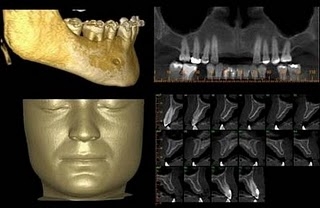

imagem 3D permite planejamento preciso e  visualização de resultados cirúrgicos

O uso da tomografia computadorizada de feixe cônico (CBCT) na avaliação dos resultados do tratamento orto-cirúrgico tem o potencial de elucidar interações entre os componentes dentário, esquelético e de tecidos moles que contribuem para a resposta à terapia aplicada. A utilização de ferramentas de superposição tridimensional (3D) permite a identificação e quantificação do deslocamento e remodelação ósseos. Com a proposta de avaliar, de forma tridimensional, os deslocamentos dos côndilos, ramos (superior, inferior e posterior) e mento após a cirurgia de avanço mandibular, os pesquisadores Alexandre Trindade Simões da Motta, Felipe de Assis Ribeiro Carvalho, Lúcia Helena Soares Cevidanes, Marco Antonio de Oliveira Almeida, da Universidade Estadual do Rio de Janeiro (UERJ) e da University of North Carolina at Chapel Hill (UNC), analisaram tomografias computadorizadas de feixe cônico das fases pré-cirúrgica e pós-cirúrgica de 27 indivíduos que apresentavam Classe II esquelética, com padrão normocefálico ou braquicefálico. A pesquisa está publicada na edição 15(5), de setembro-outubro de 2010, do Dental Press Journal of Orthodontics, sob o título “Deslocamentos esqueléticos associados à cirurgia de avanço mandibular: avaliação quantitativa tridimensional”. Uma técnica de superposição automatizada da base do crânio permitiu a avaliação de alterações esqueléticas em regiões anatômicas de interesse, e os deslocamentos foram visualizados e quantificados a partir da técnica dos mapas coloridos de superfícies. As análises mostraram que o mento apresentou deslocamento anteroinferior médio de 6,81±3,2mm, enquanto a porção inferior dos ramos apresentou movimento lateral com a cirurgia (esquerdo = 2,97±2,71mm; direito = 2,34±2,35mm). Outras regiões anatômicas mostraram deslocamento médio menor que 2mm, mas com evidente variabilidade individual. Correlações estatisticamente significativas foram positivas e moderadas. Os côndilos, bordo posterior e porção superior dos ramos apresentaram correlação bilateral, enquanto as porções superior e inferior dos ramos mostraram correlação ipsilateral. Ao finalizar o estudo, os pesquisadores concluíram que o método 3D utilizado permitiu uma precisa visualização e quantificação dos resultados cirúrgicos, destacando-se o movimento anteroinferior do mento e o deslocamento lateral da porção inferior dos ramos mandibulares, mas com considerável variabilidade individual em todas as regiões anatômicas avaliadas.